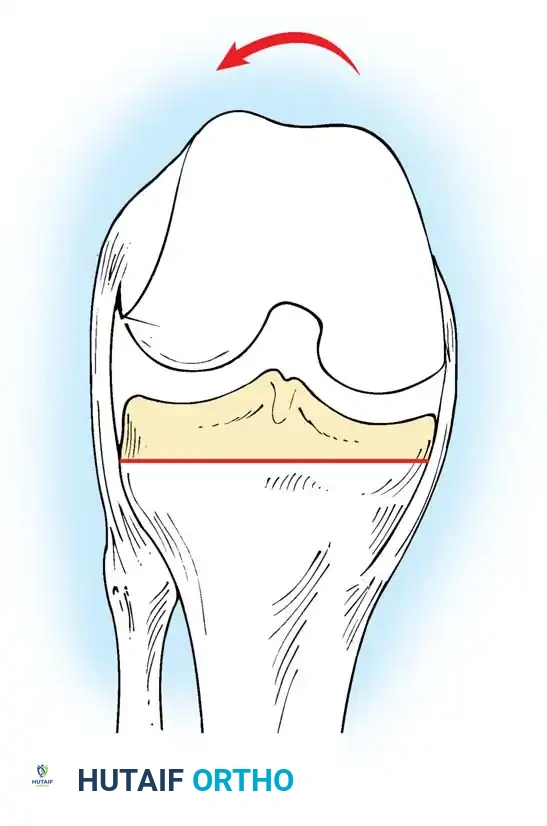

Proximal Tibial Preparation

The goal of the tibial resection is to create a flat, stable platform perpendicular to the mechanical axis of the tibia in the coronal plane, while recreating the appropriate posterior slope in the sagittal plane.

- Cut the tibia perpendicular to its mechanical axis. Extramedullary alignment guides are most commonly used, referencing the center of the tibial tubercle proximally and the center of the talus distally.

- Incorporate 0 to 5 degrees of posterior slope, depending on the implant design and the patient's native anatomy.

- Cruciate-Retaining (CR) implants typically require more posterior slope (3–7 degrees) to prevent PCL tightness in flexion.

- Posterior-Stabilized (PS) implants generally require less slope (0–3 degrees) to prevent early impingement of the tibial post against the femoral cam.

- The depth of resection is typically 8 to 10 mm from the intact lateral tibial plateau, ensuring adequate thickness for the polyethylene insert without excessively raising the joint line.